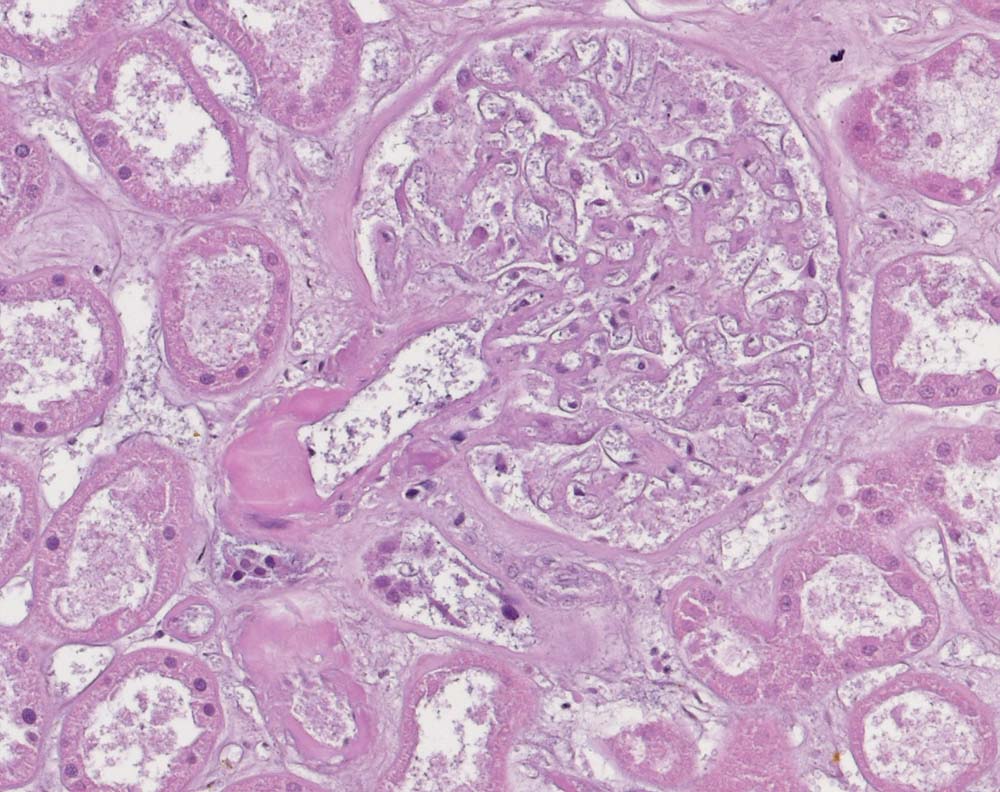

Akuter Niereninfarkt: Koagulationsnekrose

Bild aus dem Zentrum des Infarktes: Koagulationsnekrose mit nur noch schattenhaft erkennbarem Parenchym. Die Kerne sind stark abgeblasst.

Schwere allgemeine Atherosklerose. Morbus embolicus: Embolien in Nieren, Dünndarm und Hirn.

Metabolisches Syndrom. Myokardinfarkt.